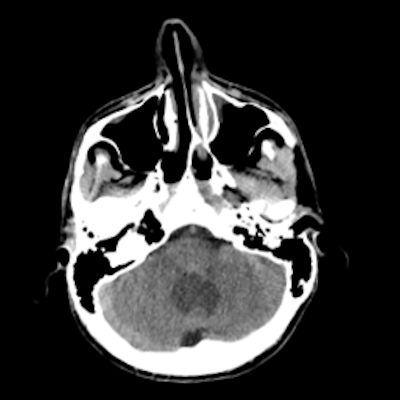

- A) Beyin BT incelemede; posterior fossada hipodens, düzgün sınırlı kistle beraber (oklar), posteriorunda 8 mm boyutunda, iyi sınırlı, kontrastsız BT’de parankim ile izodens, postkontrast görüntülerde yoğun kontrast tutulumu gösteren mural nodül komponenti (oklar) gözlenmektedir.

- BT’de tipik olarak iyi sınırlı, hipodens kistik bir lezyon ve içinde belirgin şekilde kontrastlanan mural nodül izlenir.

- Kalsifikasyon: Hemanjioblastomlarda kalsifikasyon çok nadirdir (oligodendrogliom ve ependimomlardan ayırt edici bir özellik).